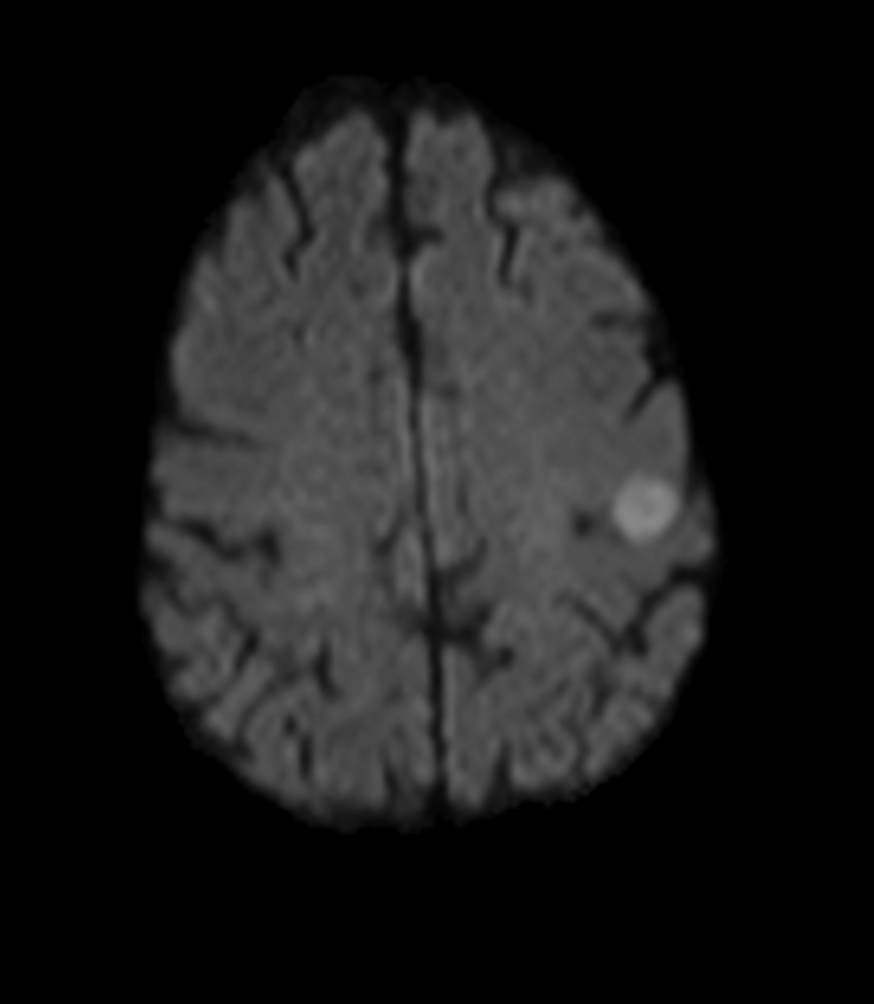

Female with one metastasis of pulmonary cancer underwent MRI simulation in the radiotherapy positioning mask on Ingenia MR-RT 1.5T before stereotactic radiation therapy with 25 Gy in 3 fractions.

Axial DWI (b1000)